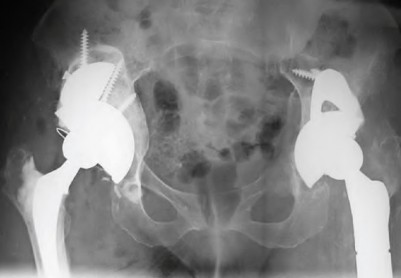

Question 32

A 45-year-old female with developmental dysplasia of the hip (DDH) presents for THA. Preoperative radiographs show the femoral head is subluxated, with 80% proximal migration relative to the height of the normal true acetabulum. Based on the Crowe classification, what type of dysplasia does she have?

Question 58

A 35-year-old female with developmental dysplasia of the hip (DDH) Crowe Type IV is undergoing THA. The surgeon plans to place the acetabular component in the true anatomic hip center. If the leg is lengthened >4 cm without a subtrochanteric shortening osteotomy, which nerve division is most susceptible to traction injury?

Question 59

Radiographs of a failed THA demonstrate severe periprosthetic osteolysis. The acetabular component has migrated 4 cm superiorly and 2 cm medially past Kohler's line, and the radiographic teardrop is completely destroyed. Which Paprosky acetabular defect is present?